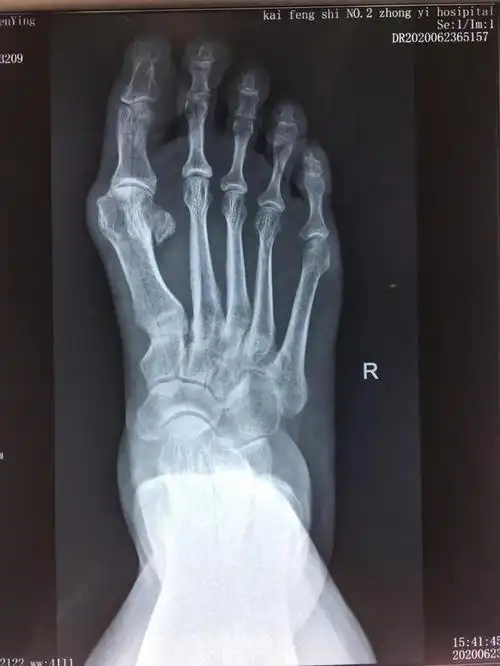

微创手术治疗拇外翻,医保报销,费用低,术后即可下地

脚骨x光片术前术后对比在油管上查了很多关于拇外翻手术的视频(血腥

做大脚骨手术一定要上钢板吗微创效果佳恢复快